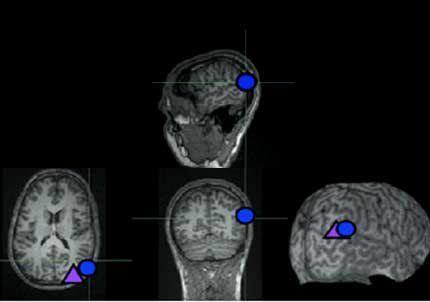

Estudios anteriores mostraron que una región del cerebro denominada unión derechatemporoparietal (ubicada detrás del oído derecho) está muy activa cuando una persona piensa en lasintenciones, pensamientos y creencias de otra persona y cuál será el resultado de un acto enparticular. Enesta investigación, investigadores del MIT (Massachusetts Institute of Technology) perturbaronla actividad en esta zona cerebral aplicando una corriente eléctrica con un campo magnéticoaplicado sobre el cuero cabelludo y luego le pidieron a los participantes del estudio que leyeranuna serie de guiones que planteaban interrogantes morales y calificaran la moralidad de lasacciones de los personajes. En otro experimento, las personas sufrieron una descarga de corriente electromagnética de 500milisegundos en el mismo momento en el cual se les pedía realizar una evaluación moral. Por ejemplo, los investigadores invitaron a decir si estaba bien que el personaje dejara asu amiga caminar sobre un puente sabiendo que éste era peligroso. En ambos experimentos laspersonas estudiadas indicaron que no había nada moralmente reprensible. El estudio muestra de "forma sorprendente" que esta zona cerebral situada en la superficiedel cerebro juega un papel clave para elaborar percepciones morales, indicó Liane Young, del MIT. "El hecho de simplemente aplicar un campo magnético sobre una parte específica del cerebro y modificar la evaluación moral es absolutamente pasmosa". Hasta ahora pensábamos que la moralidad provenía de "procesos mentales muy complejos",añadió.